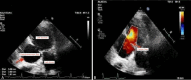

Two Rare Complications of Post Myocardial Infarction: A Case Report